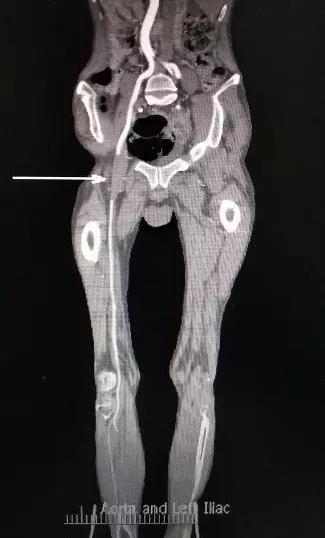

▲ 术前下肢CTA可见左股动脉闭塞